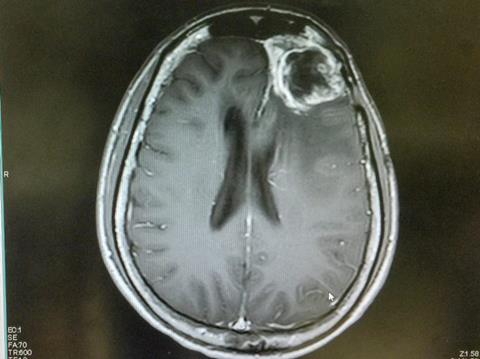

A team of researchers from the San Raffaele-Telethon Institute for Gene Therapy (SR-TIGET, Milan) have announced a novel gene therapy-based approach to bolster chimeric antigen receptor (CAR) T cell therapy for glioblastoma - one of the most aggressive and treatment-resistant brain tumours. The study, led by Nadia Coltella and Luigi Naldini and published in Science Translational Medicine, demonstrates how localised immune stimulation within the tumour microenvironment (TME) not only restores CAR-T cell activity but also recruits the body’s broader immune system to fight the tumour.

The strategy uses gene therapy to target immune-stimulating cytokines directly into the tumour, enabling a “private crosstalk” with CAR-T cells. This boosts CAR-T persistence, triggers wider immune activation and significantly delays tumour growth in preclinical glioblastoma models.

“Solid tumours like glioblastoma have been notoriously difficult for CAR-T cells to penetrate and control,” explains Dr Frederico Rossari, first author of the study. “By reprogramming a population of tumour-infiltrating macrophages to deliver cytokines directly into the tumour, we’ve morphed the immunosuppressive TME into one supportive of immune cells, thus allowing CAR T cells to better persist, become activated and attack tumour cells.”